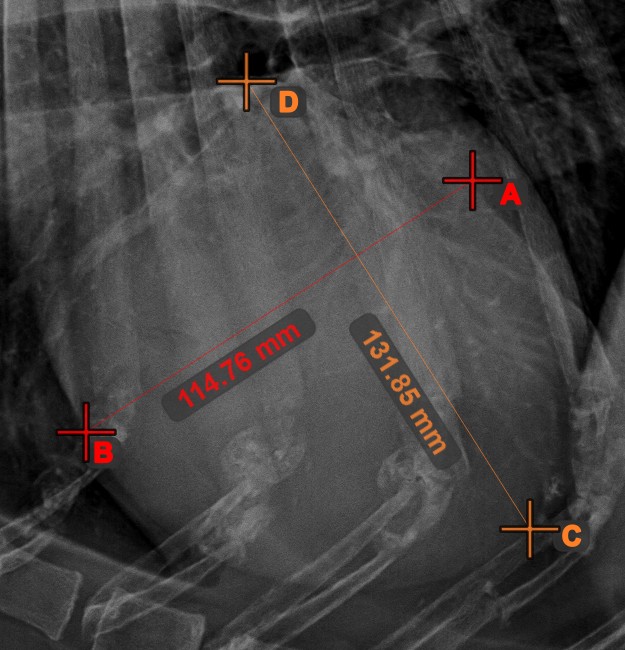

Center Point of Line¶

Identify and mark the center point of a new or existing line measurement on the scene by using the Center Point of Line tool.

Select the tool from the left toolbar and assign it to one of the available mouse buttons. Place the start and end points on the scene, select them from already existing points on the image, or select an already drawn line from the scene. The center point of the line will be automatically calculated and placed on the scene. The center point of each line will always be marked with the letter C.

Line Intersection¶

Quickly and accurately locate and mark the intersection point between two existing lines by using the Line Intersection tool.

Select the tool from the left toolbar and assign it to one of the available mouse buttons. Select two lines that have already been drawn on the scene to complete the measurement. The intersection point of the line will be automatically calculated and marked on the scene. The intersection point of two lines will always be marked with the letter X.

Information

If two lines do not intersect directly, the intersection point of their extended projections on the scene will be marked.